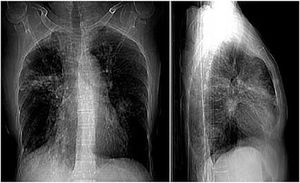

Case History: 60-year-old female with complaint of breathlessness during rest, unrelated to smoke/dust; non-purulent non-blood stained whitish expectorant in cough; fever.